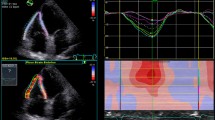

CMR image analysis

Cine images were analyzed using semi-automated cvi42 software (Circle Cardiovascular Imaging, Calgary, Canada) by a single experienced observer (PK), blinded to all clinical data. All volumetric and mass data were indexed to body surface area (BSA). Ventricular volumes (see Fig. 1), ejection fraction and LV mass (excluding papillary muscles) were calculated from the short-axis cine stack as previously described [10, 15]. The biplane method, excluding the appendage and pulmonary veins was used to measure maximal, minimal left atrial volumes (LAVmax, LAVmin) and derive left atrial ejection fraction (LAEF) [11]. A cut-off RVEF value of < 47% was used to define RVD based upon existing normative data from the published literature utilizing the same technique as in our study [16] as well as from our own healthy control data whereby the lower limit of RVEF was also 47%. Qualitative LGE assessment was undertaken by 2 experienced operators to define the presence of MI as per standard criteria [15, 17]. In cases of disagreement, final adjudication was deferred to a third operator (GPM). As previously reported by our group with excellent reproducibility [18] and intra/inter-observer agreements [15], extracellular volume (ECV) and indexed ECV were quantified from mid short-axis LV slice T1 maps.